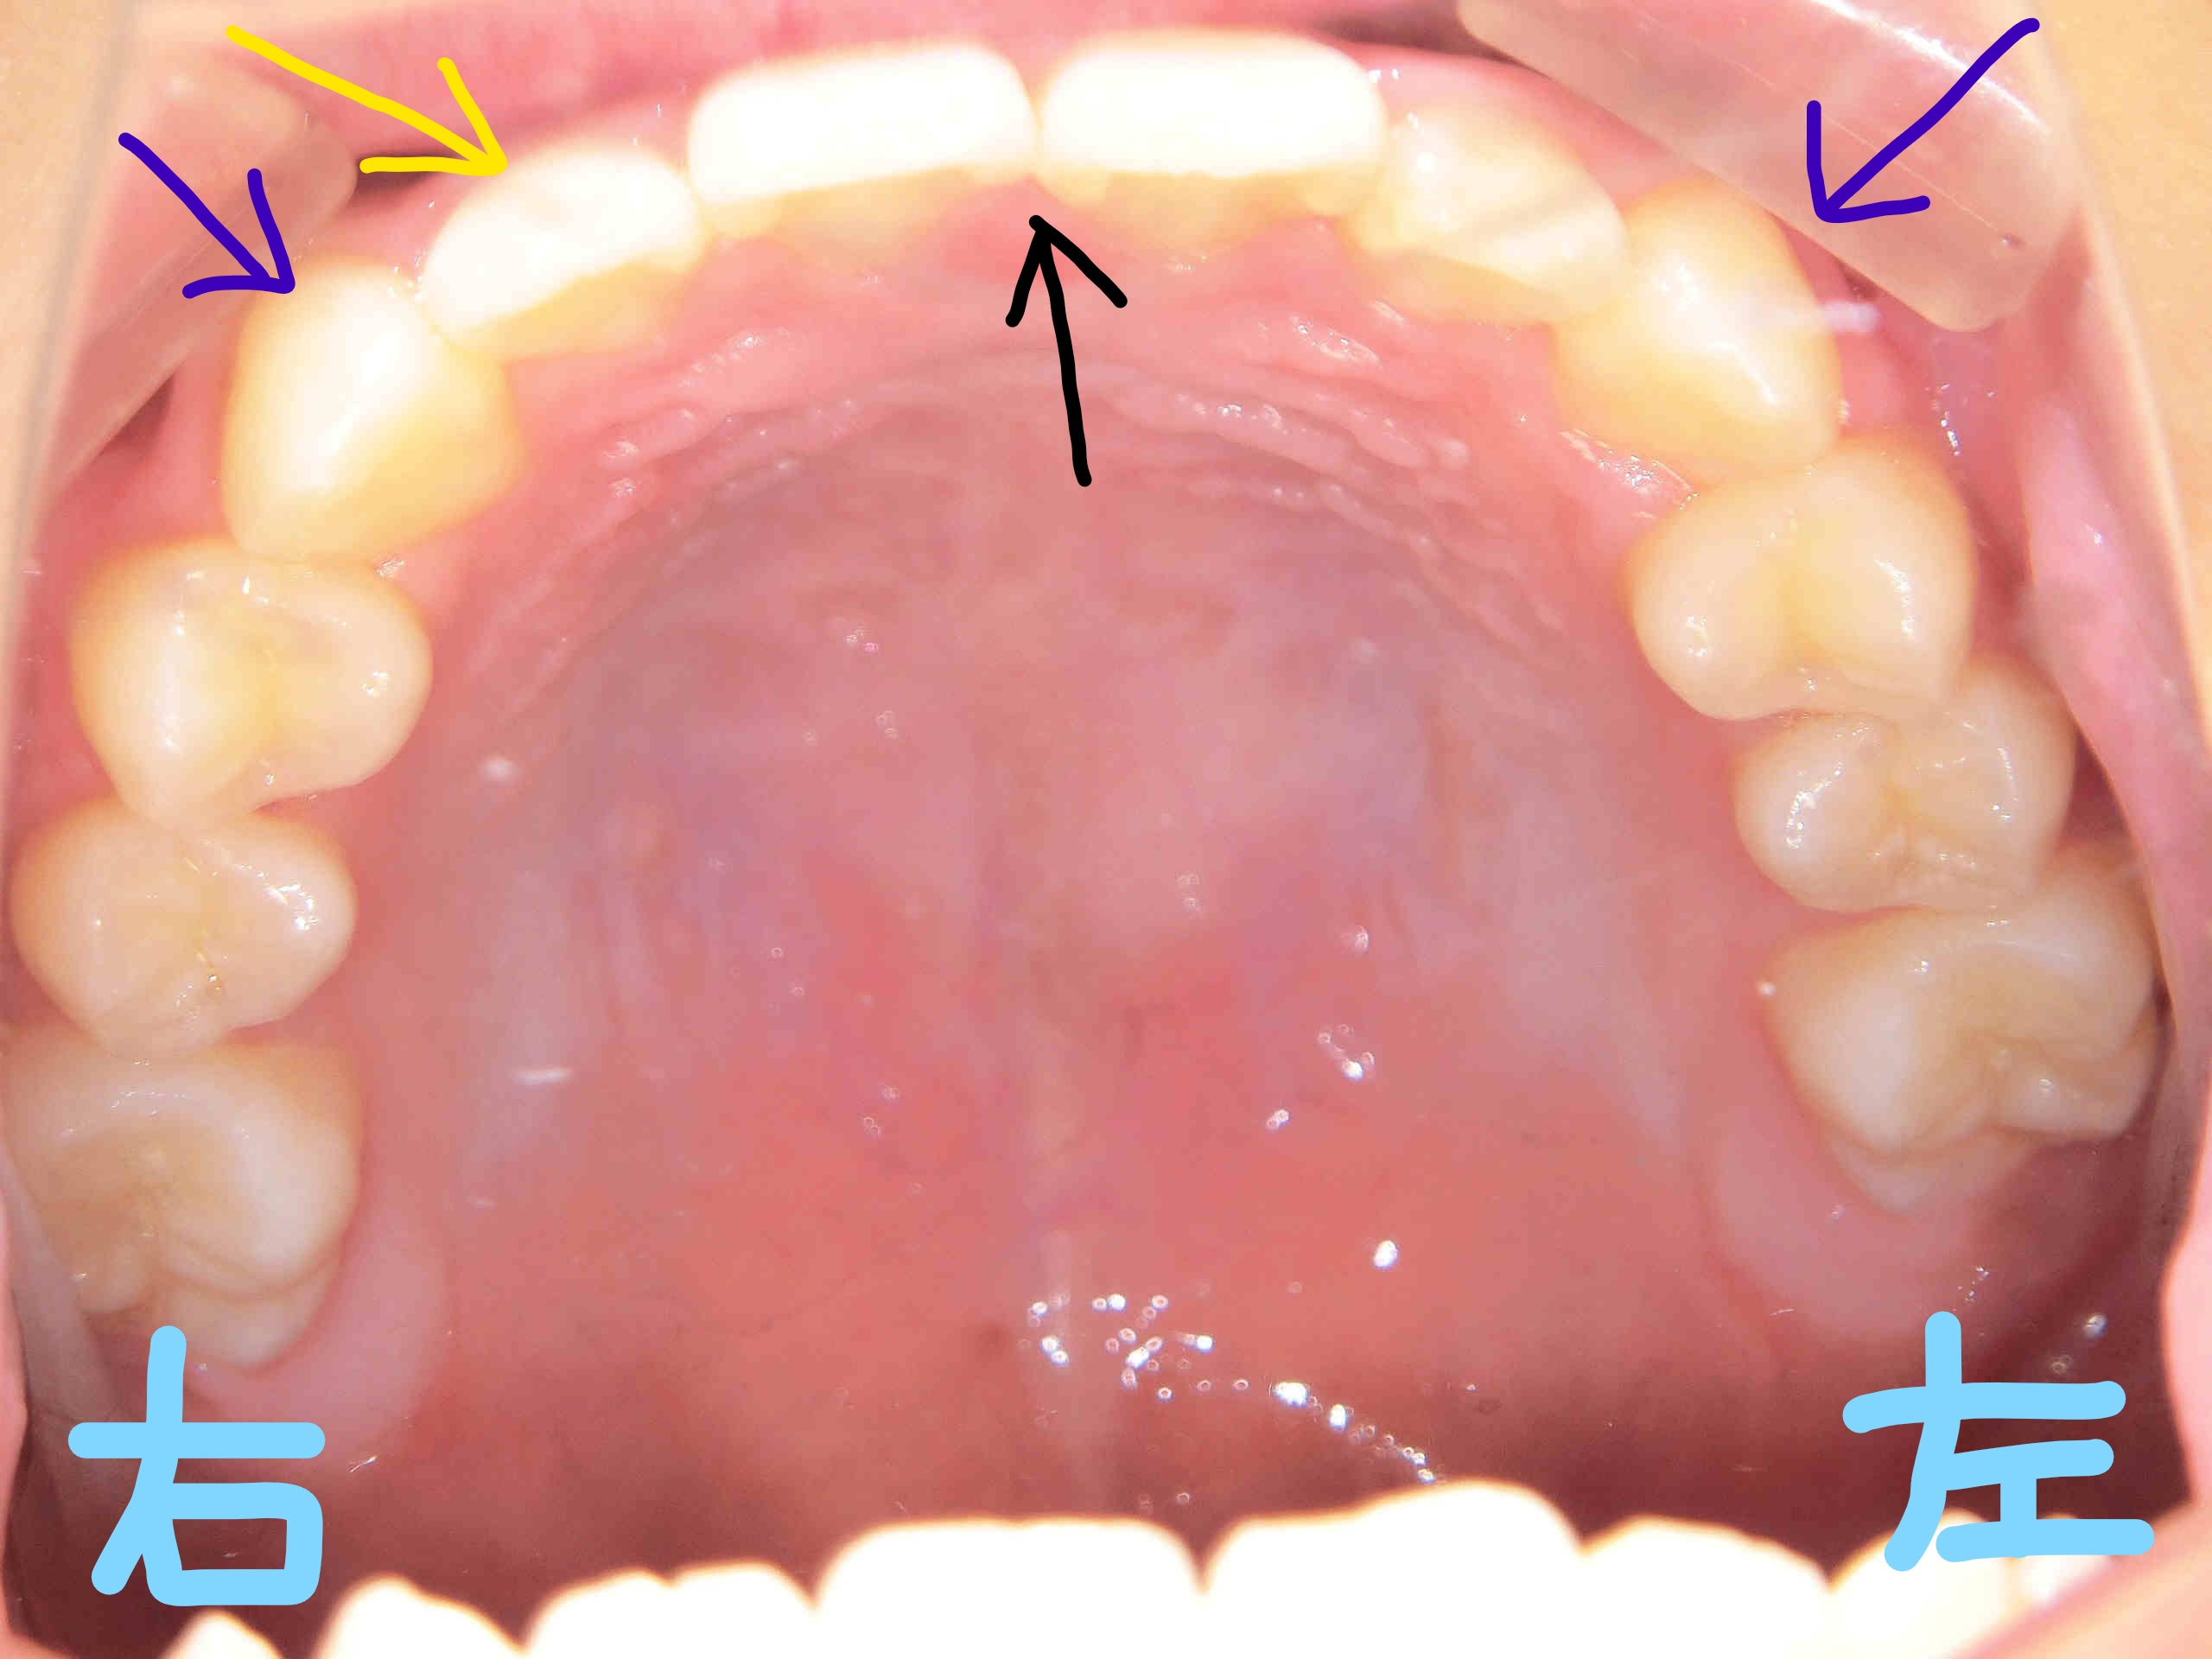

左上の写真は上顎を下から見た写真、右上は下顎を上から見た写真です。第二大臼歯が完全に萌出するまでは経過観察が必要ですが、上下顎ともに歯列の整列が進んでいる様子が確認されます。